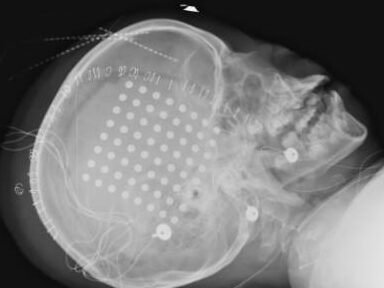

⦁ การวาง Subdural grid implantation

จับจุดชักบนผิวสมอง

⦁ การผ่าตัด Stereotactic encephalography (SEEG)

โดยไม่ต้องเปิดกะโหลกศีรษะ